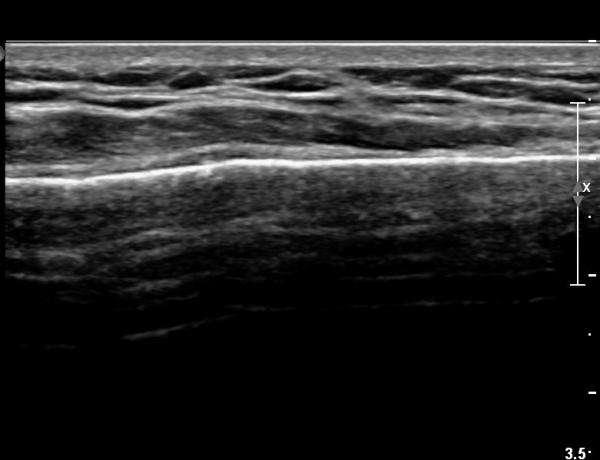

Äá¾Ë»À Á¾´Ü¸é°Ë»ç¿¡¼­ Äá¾Ë »À ±ÙÀ§ºÎÀÇ ÇÇÁú°ñ °ß¿­ÀÌ °üÂûµÊ(»çÁö 4).